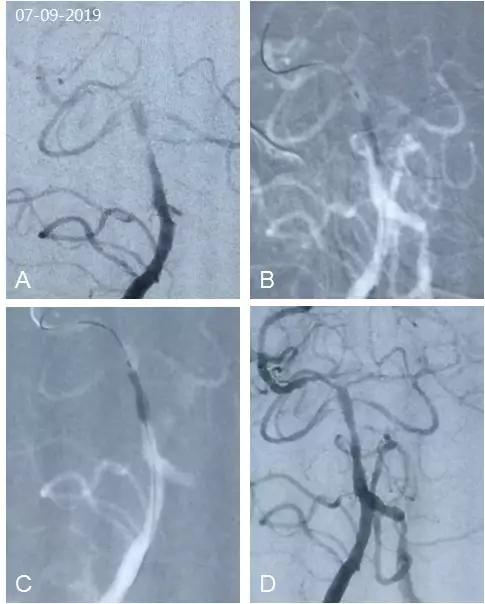

全麻下右股动脉入路,将6F导引导管头端置于右椎动脉V2远端,造影显示基底动脉中远段重度狭窄,双侧大脑后动脉顺行显影欠佳(图5A)。路径图下将Transend(0.014"300 cm)微导丝越过狭窄段,导丝头端放置于右大脑后动脉P2段,沿导丝送入Maverick(2.0 mm×15 mm)球囊于狭窄处行预扩张(图5B)。因双侧大脑后动脉P1段纤细,综合考虑术中选择放置球囊扩张支架。沿微导丝送入APOLLO®(2.5 mm×08 mm)球囊支架,准确定位于狭窄处,缓慢扩张球囊至5.5大气压,此时支架近端扩张良好,中远端尚有轻度残余狭窄(图5C)。考虑支架已经释放贴壁,若进一步扩张支架可能造成穿支动脉闭塞,未进一步扩张球囊。回撤微导丝及支架球囊,造影复查提示支架贴壁可,残余狭窄小于20%(图5D),前向血流良好,TICI分级3级,观察15 min无改变,结束手术。

图5

本例基底动脉中远段重度狭窄,治疗过程中发现双大脑后动脉P1段纤细,放置Wingspan支架或者经导管释放自膨支架有潜在损伤大脑后动脉着陆区风险,故选择APOLLO®球囊扩张支架。释放支架时,缓慢扩张球囊,待球囊与远近管壁充分贴合,虽有一定程度“束腰征”,但支架已经贴壁释放。本例若追求球囊完全充盈,支架释放后会有更好的影像学结果,但穿支卒中风险也显著增加。